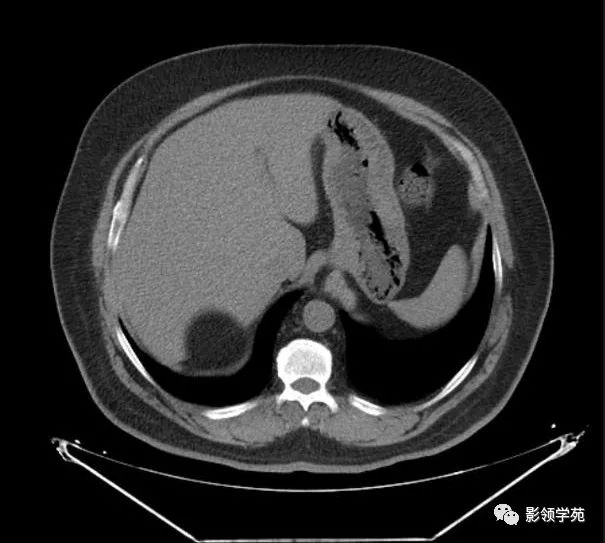

核磁诊断:左侧肾上腺髓样脂肪瘤可能,肿瘤大小约10cm,位于脾门及胰体

图片尺寸2296x1910